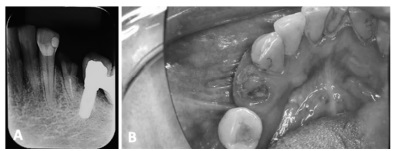

Um paciente de 45 anos de idade, hipertenso, diabético tipo II, controlado, faz uso diário de metformina 500 mg e losartana 50 mg. Relata ter sido encaminhado para extração da raiz residual do dente 34. Refere dor leve no local e fobia a tratamento odontológico e nega qualquer outra comorbidade. A seguir, a imagem A corresponde à radiografia periapical da região inferior esquerda, que revela dente 34 com restauração distal, presença de resto radicular com tratamento endodôntico relacionado ao dente 34 e presença de prótese implantosuportada com pôntico relacionada à área do dente 35; a imagem B, por sua vez, corresponde à imagem intrabucal da região de mandíbula esquerda, evidenciando a presença dos dentes anteriores, com cálculo supragengival na região lingual, gengiva inflamada e resto radicular correspondente à área do dente 34. Observa-se, ainda, coroa protética na área do dente 35.